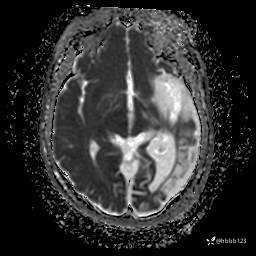

T2 Flair: